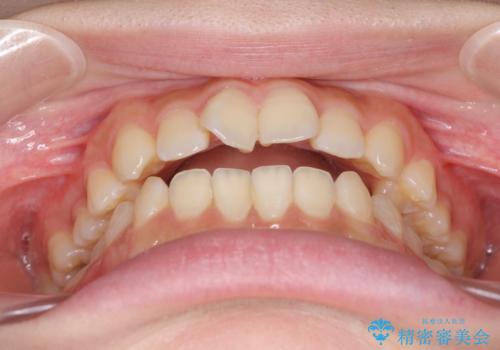

- 前歯のオープンバイトを気にして来院された患者様です。

上下前歯の前後位置が大きくずれていたため、上顎左右第一小臼歯2本を抜歯してワイヤー装置による矯正治療を行うこととしました。

オープンバイトの原因は舌の突出癖であり、癖が改善されないと治療経過に影響を及ぼすため、舌のトレーニングを指示しました。